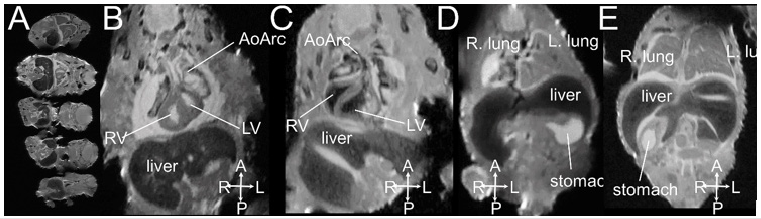

MRI is based on the detection of protons utilizing low-energy radio-frequency (RF) waves in magnetic fields to form images without ionizing radiation. MRI has excellent intrinsic soft tissue contrast because the relaxation characteristics of water protons are governed by the micro-environment of each tissue 11. With the development of small-board high-field magnets and small micro-RF coils, micro-MRI is capable of very high-resolution 3D imaging of mouse embryos with excellent contrast 26-29, thus termed “MR Microscopy” 30. Hence, micro-MRI is a suitable imaging modality for “digital pathology” or “virtual histology” 11, 28, 31, 32 for phenotyping and characterizing mouse embryos without tissue sectioning as conventional histology. Formalin fixed mouse embryos or newborn pups can be soaked in 0.05 % gadolinium (Gd) solution for one to a few days for contrast enhancement prior to imaging. Figure 2 shows multiple mouse embryos harvested on the embryonic day E16.5 imaged by micro-MRI with 33 m X 46 m X 46 m spatial resolution. Congenital structural birth defects can be identified (Figures 2C-2E).

Figure 2: An example of ex vivo 3D micro-MRI of formalin-fixed E16.5 mouse embryos imaged at 33 m X 46 m X 46 m spatial resolution. (A) 5 fetuses can be imaged at the same time; (B, D) normal embryos; (C) mutant with right aortic arch; (E) mutant with right stomach. Abbreviations: AoArc: aortic arch; LV: left ventricles; RV: right ventricle; The arrowheads indicate body axis: A-anterior; P: posterior; L: left; R-right.